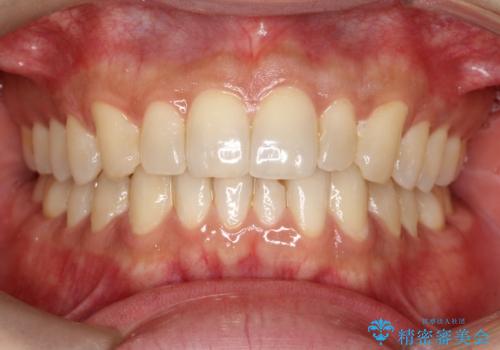

- 前歯の歯並びの改善を希望され来院された患者様です。

見た目、嚙み合わせ及び、治療期間や施術内容に大変ご満足いただきました。